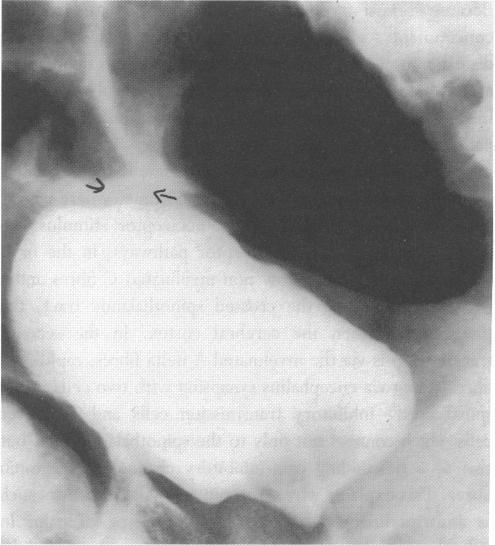

Ascites and apparent renal failure treated with a Foley catheter.